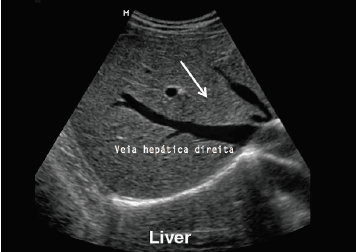

Com base na segmentação sugerida por Couinaud e a imagem de ultrassonografia na Figura (abaixo), assinale a alternativa que indica corretamente o segmento hepático apontado pela seta branca.

Figura: Ultrassonografia hepática.

A

IV

B

V

C

VI

D

VII

E

VIII